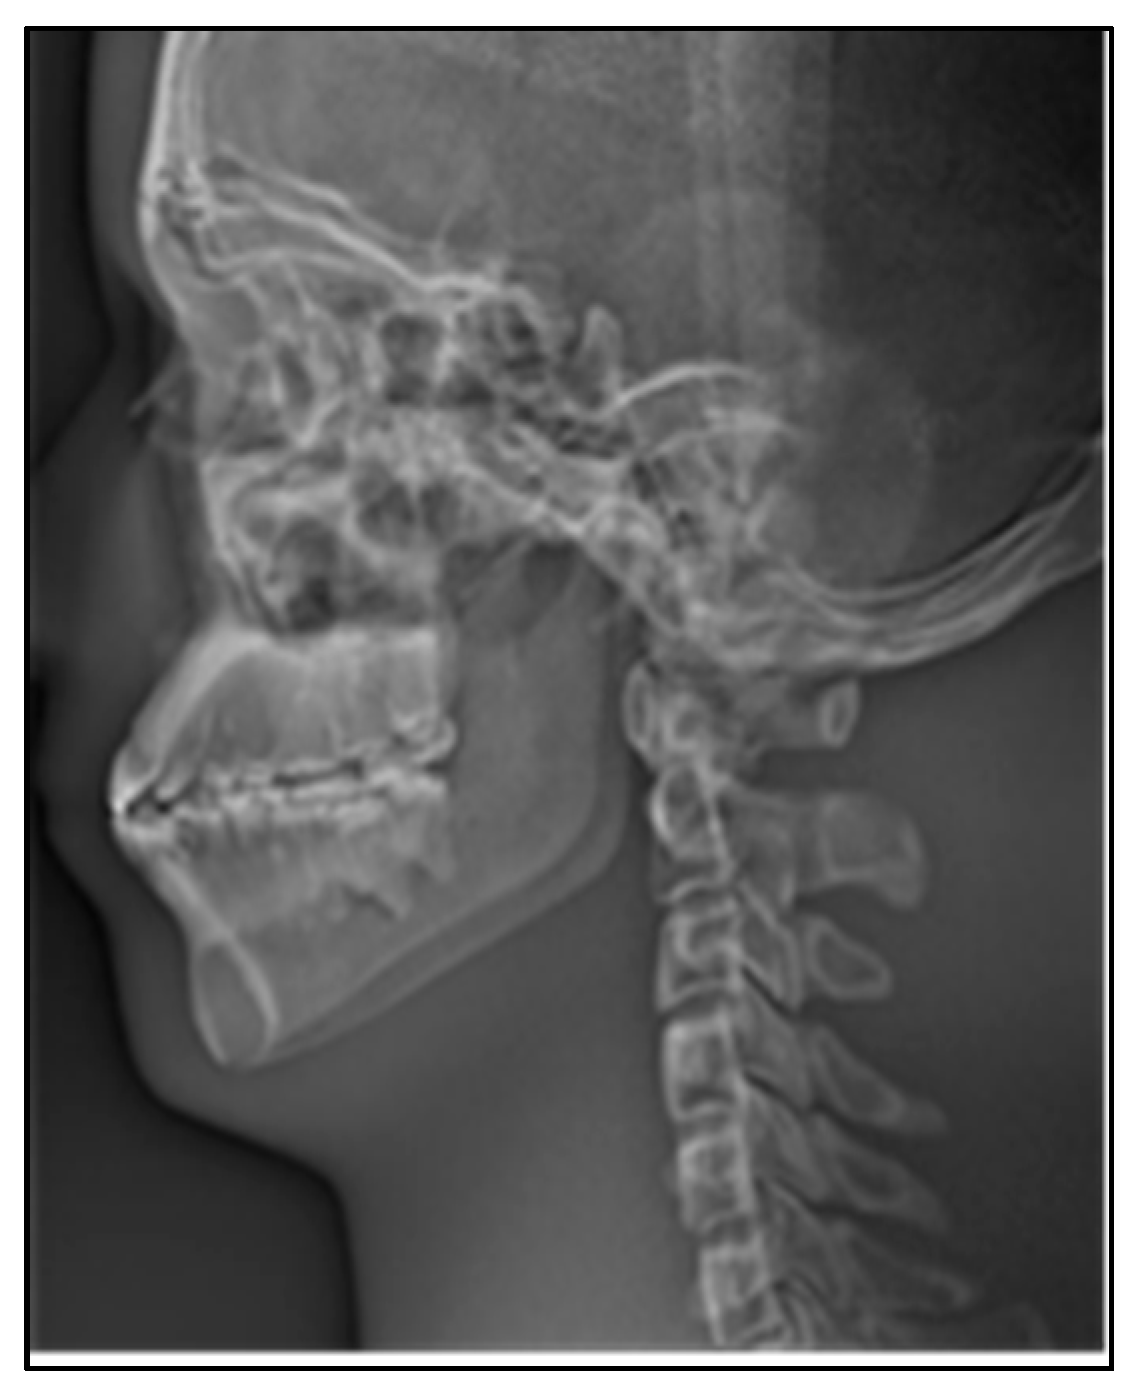

As shown in Figure 15a, the continuous stitching strategy was adopted in this paper to complete the stitching of 480 original sequence images. Figure 15b is an image of the anterior part of the skull obtained from serial image stitching, which is mainly used for the diagnosis and postoperative evaluation of oral deformity. Figure 15c is a stitching image of the posterior portion of the skull, which is used to diagnose the spine. Figure 15b,c obtained the final cranial lateral panoramic image of the oral cavity through a round of stitching.

Figure 15.

Stitching process of lateral cephalogram. (a) The image sequence is stitched in multiple rounds, (b) results of anterior skull stitching, (c) results of posterior skull stitching.

In X-ray imaging, the higher the density of the tissue, the more obvious the absorption of X-rays. In order to make the images more detailed for clinical diagnosis, therefore we need to reverse color manipulation of the stitching panoramic image, as shown in Figure 17.

Figure 17.

Lateral cephalogram after reverse color manipulation.